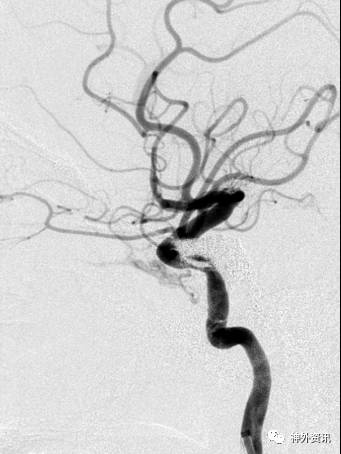

病例一